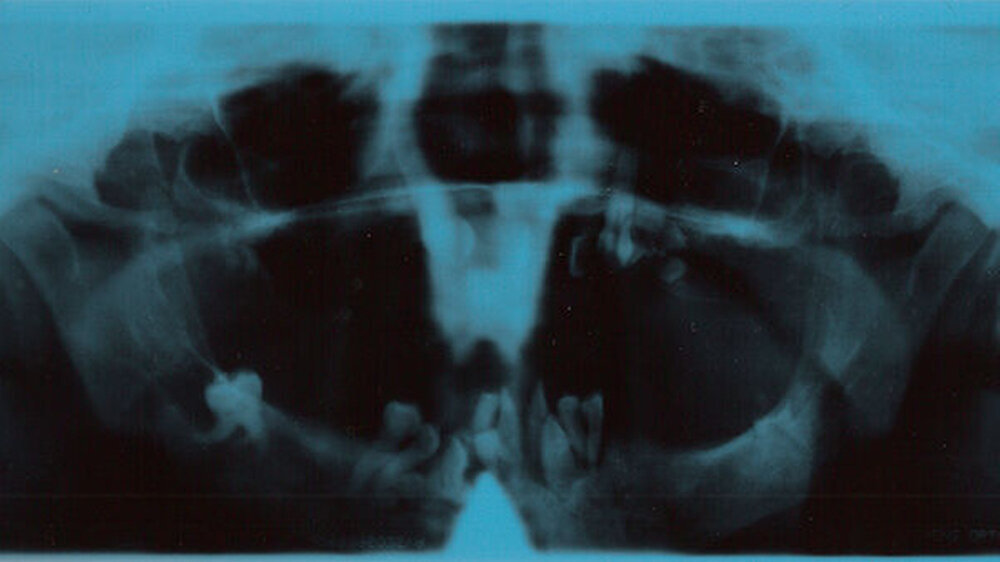

Ein daraufhin angefertigtes OPG belegte den vorgefundenen Zustand auf beeindruckende Weise (Abbildung 5). Anamnestisch ließ sich keinerlei Erklärung über die Ursache und das Zustandekommen dieser merkwürdigen Situation finden. Die Patientin konnte oder wollte darüber keine Auskunft erteilen. Nachdem ihr der wiederhergestellte Zahnersatz ausgehändigt worden war, erschien die Patientin trotz Terminvergabe nicht wieder in unserer Praxis."